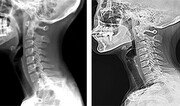

목을 숙여 스마트폰을 보는 습관 등으로 목, 어깨 등에 뻐근한 통증을 호소하는 ‘일자목 증후군’ 환자가 매년 증가하고 있다. 일자목 증후군이란 목을 길게 빼는 자세 때문에 C자 형태의 경추가 일자로 변형되는 질환이다. 국민건강보험공단에 따르면 ‘일자목 증후군’ 환자는 2011년 239만7000여 명에서 2016년 269만6000여 명으로 5년 새 30만 명 가까이 늘었다. 연평균 2.4% 증가한 수치다. 또 2016년 환자 연령대별로는 50대(23.8%)가 가장 많았고, 40대(21%) 30대(15.3%)의 순이다. 이장우 국민건강보험공단 일산병원 재활의학과 교수는 “근래 컴퓨터나 스마트폰 사용이 일상화되면서 발생 연령대가 점차 낮아지고 있다”고 말했다. 일자목 증후군의 주된 원인은 잘못된 자세와 동작이다. 잘못된 자세가 골격의 변형까지 일으키는 데다 나이가 들면 목 주변 근육의 근력이 약해지고 척추에도 퇴행성 변화가 발생해 통증도 심해진다. 일자목 증후군을 방치하면 목 부위 통증뿐 아니라 두통과 어깨 통증에도 시달릴 수 있다. 목 척추가 정상적으로 배열돼 있을 때는 머리의 무게가 목뼈와 디스크 쪽으로 분배되지만, 일자목에서는 머리의 무게가 목 주위 근육, 인대, 관절 등에 많은 부하가 걸린다. 일자목 증후군이 심해지면 수술을 받아야 하는 경우도 있어 무엇보다 예방이 중요하다. 평소 어깨를 편 자세를 유지하고 양쪽 어깨를 벌려 흉곽을 확장하는 방향으로 스트레칭을 하면 도움이 된다. 대개 목 뒤쪽 근육이 짧아져 있기 때문에 손을 머리 위쪽 방향으로 올려 후두부에 오게 한 다음 고개를 아래로 당기는 방법으로 스트레칭을 해주면 좋다. 바로 앉은 자세에서 손을 이용해 목을 밀고, 손으로 미는 방향의 반대쪽으로 목에 힘을 주면서 운동하는 것이 좋다. 앞뒤와 양옆 등 네 방향으로 운동한다. 컴퓨터 모니터는 팔을 뻗으면 닿을 정도의 거리에 오도록 하고, 앉은 자세에서 눈이 모니터의 중앙을 보도록 높이를 조절한다. 스마트폰 사용 시 목이 과도하게 굴곡이 되지 않도록 눈높이와 거리를 함께 조절한다. 오랜 시간 사용할 때는 30분에 한 번씩 스트레칭을 해준다. 자리에서 일어나 서서 하면 허리 건강도 챙길 수 있다. 김하경 기자 whatsup@donga.com}